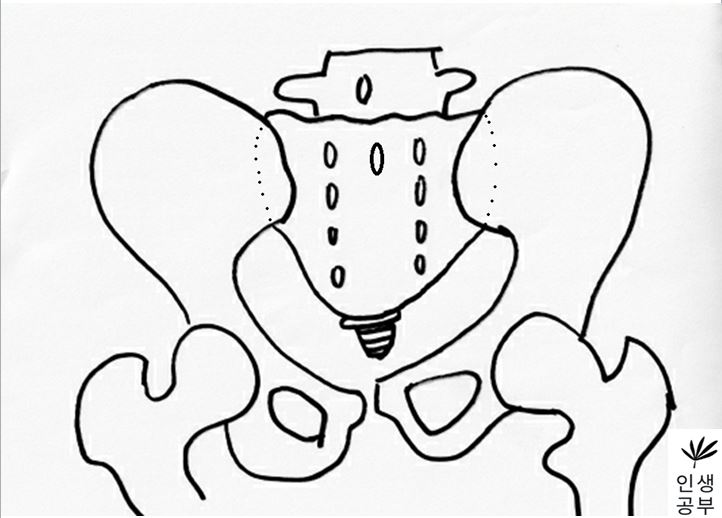

X-RAY에서 골반이 EX/IN를 어떻게 알 수 있는지에 대해서 알아보겠습니다. EX는 한쪽 골반(EX 측 골반)이 엉치뼈(Sacrum)가 있는 방향의 반대 방향으로 (배꼽 쪽으로) 가는 것을 말하고 반대로 IN은 엉치뼈(Sacrum)가 있는 방향으로 한쪽 골반(IN 측 골반)이 향하는 것을 가리킵니다. 그럼 어떻게 알 수 있는지에 대해서 선 그리는 방법을 통해서 알아보겠습니다.

1. 골반 X-ray 선 그리는 방법(EX/IN)

1) X-ray를 준비합니다.

2) 대퇴골두(Femoral head) 최상단에 양쪽에 각각 한개씩 점을 찍어줍니다.

3) 두 점을 연결하는 선을 긋습니다. 이 선의 이름은 대퇴골두선(FHL : Femur Head Line)이라고 합니다.

4) 1번째나 2번째 엉치뼈 결절(sacral tubercle) 정가운데 점을 찍어줍니다.

5) 치골결합(pubic symphysis) 정가운데에도 점을 찍어줍니다.

6) 1번째나 2번째 엉치뼈 결절(sacral tubercle) 정가운데 찍은 점에서 대퇴골두선(FHL : Femur Head Line)을 기준으로 수직인 선을 긋습니다.

선을 그었을 때 점이 있는 쪽 골반이 IN이 됐다는 뜻이고, 없는 쪽은 EX 되었다는 뜻입니다.